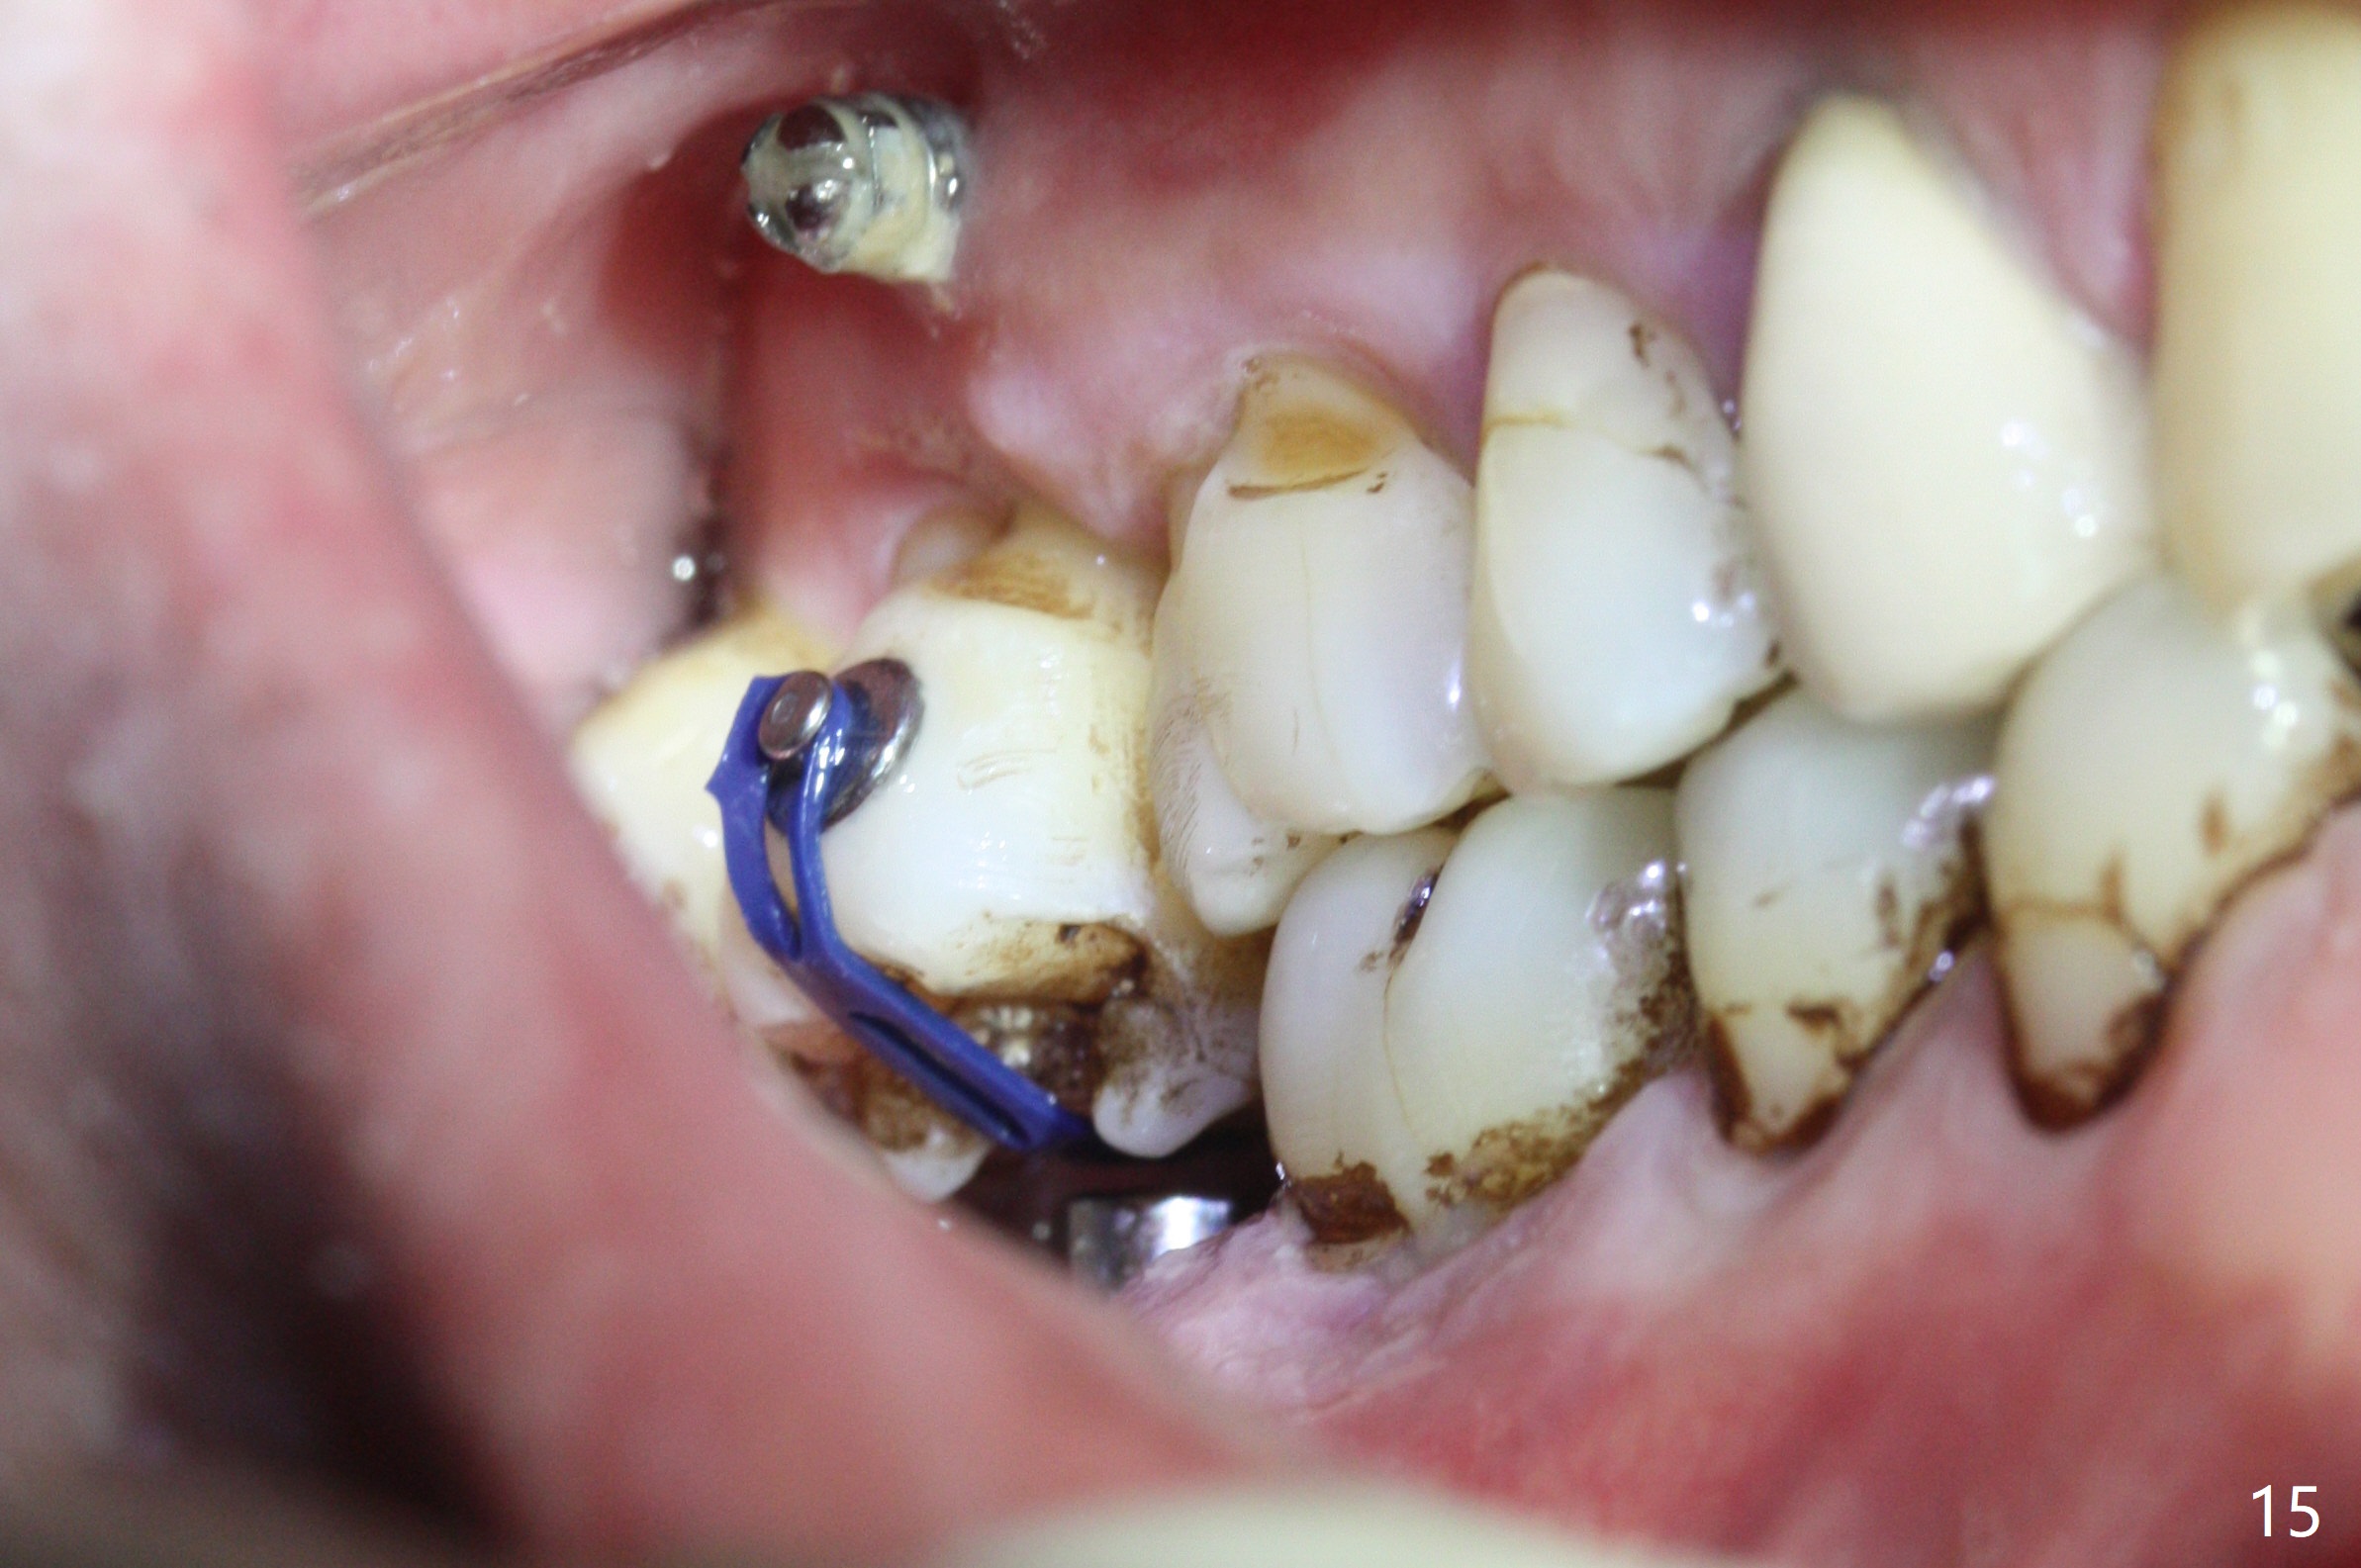

The buccal implant becomes loose in 2-3 months. When the wound heals (Fig.9 <), a 1.6x`10 mm implant is placed with the help of PAs for trajectory (Fig.10,11) and in the nonkeratinized gingiva (higher, the crestal bone may have been traumatized by previous implant placement, Fig.12). Two months later, the tooth #2 is partially intruded (Fig.13). A provisional (Fig.14 P) is fabricated in the osteointegrated implant at #31 with supraocclusion so that the remaining dentition has no occlusal contact (*). The periodontally compromised tooth #2 becomes in buccoversion in 2 months. The provisional is removed, while a lingual button is placed in the buccal surface of the tooth #2 (Fig.15). With power chain attached to the lingual mini-implant, the tooth #2 is lingualized in 2 months. The provisional and the implants are reused for final intrusion (Fig.16). The treatment is nearly 11 months. The buccal implant, although placed in the movable mucosa, remains stable and healthy (Fig.17). The tooth #1, as a guiding plane (to prevent #2 from distalization during intrusion), is not extracted after intrusion is completed.